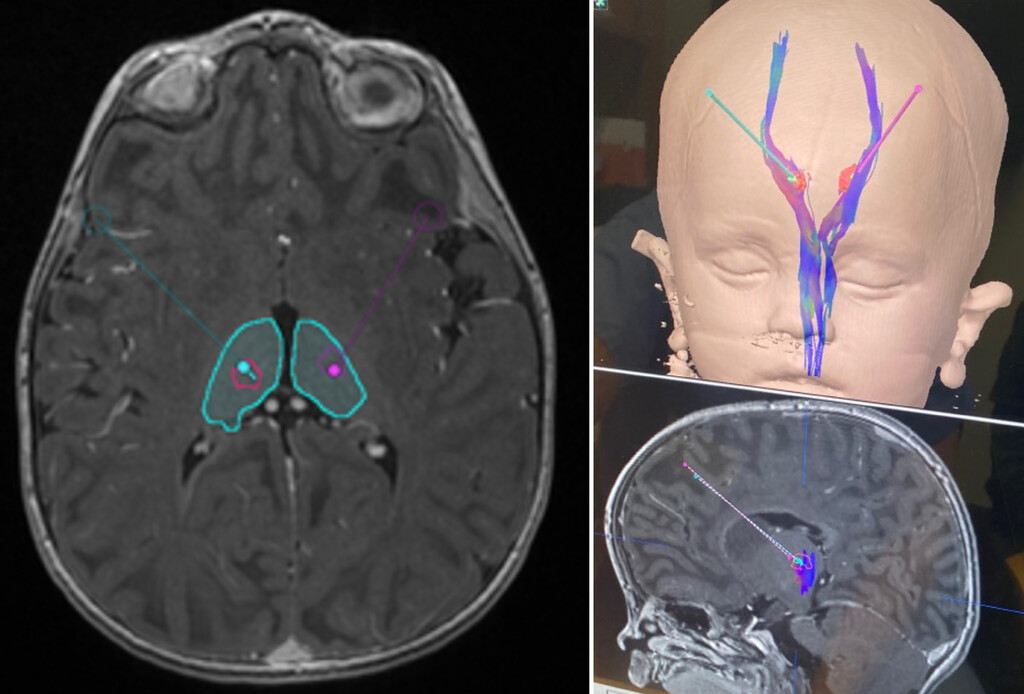

#OnlineFirst: Robot-assisted intrathalamic infusion for gene therapy in young children: surgical considerations https://t.co/QViOWUYewD

1